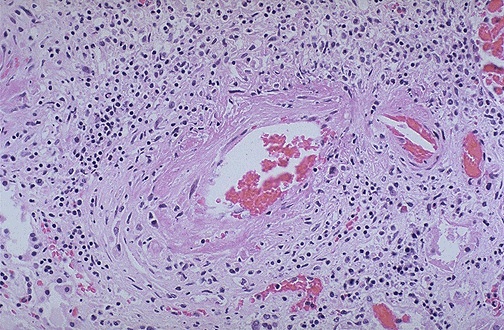

| Here is a vasculitis of a renal arterial branch. Lymphocytes are scattered in and around the vessel. This happens to be the classic form of polyarteritis nodosa (PAN), a systemic vasculitis that most often affects the kidneys. The ANCA serology is often negative. |